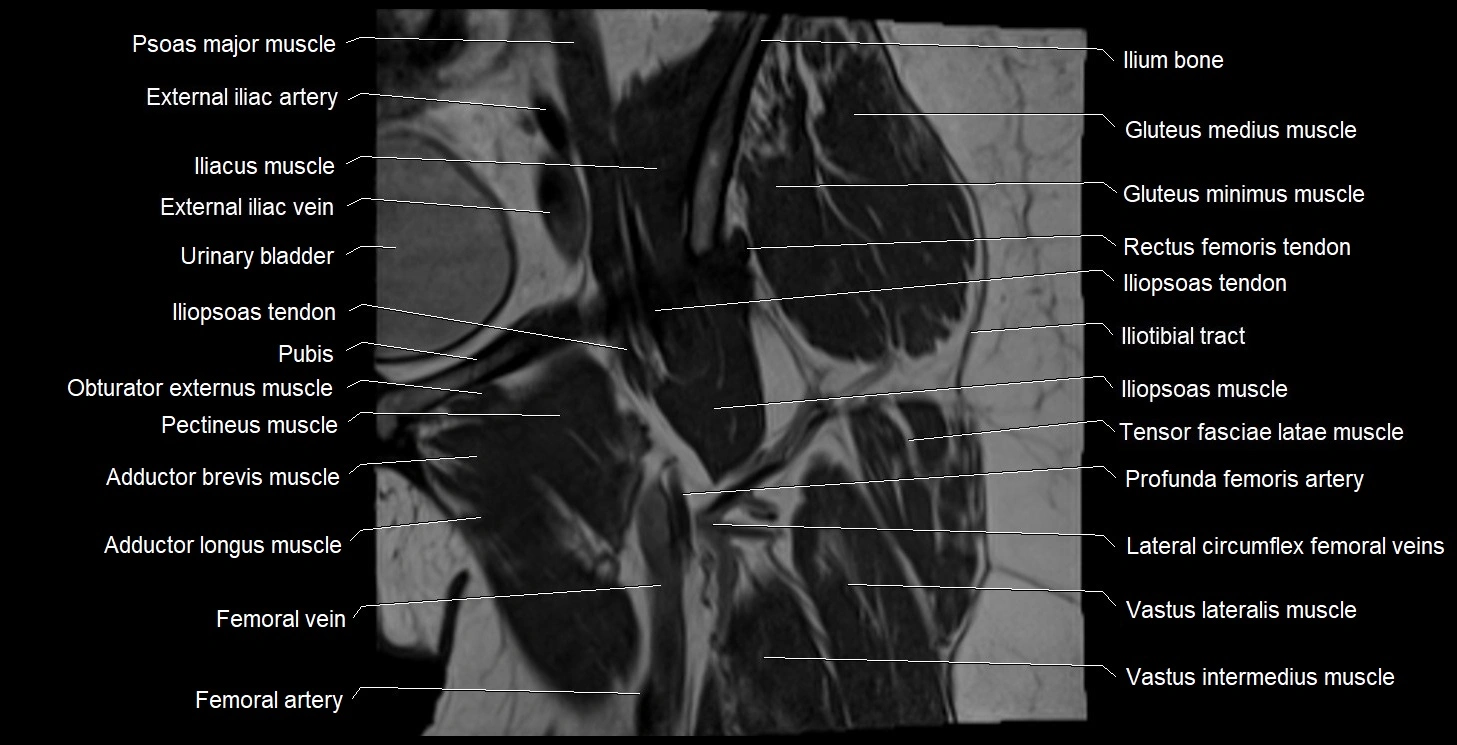

- Adductor brevis muscle

- Adductor longus muscle

- Femoral artery

- Femoral vein

- Iliopsoas muscle

- Iliopsoas tendon

- Iliotibial tract

- Ilium bone

- Obturator externus muscle

- Pectineus muscle

- Psoas major muscle

- Tensor fasciae latae muscle

- Vastus intermedius muscle

- Vastus lateralis muscle